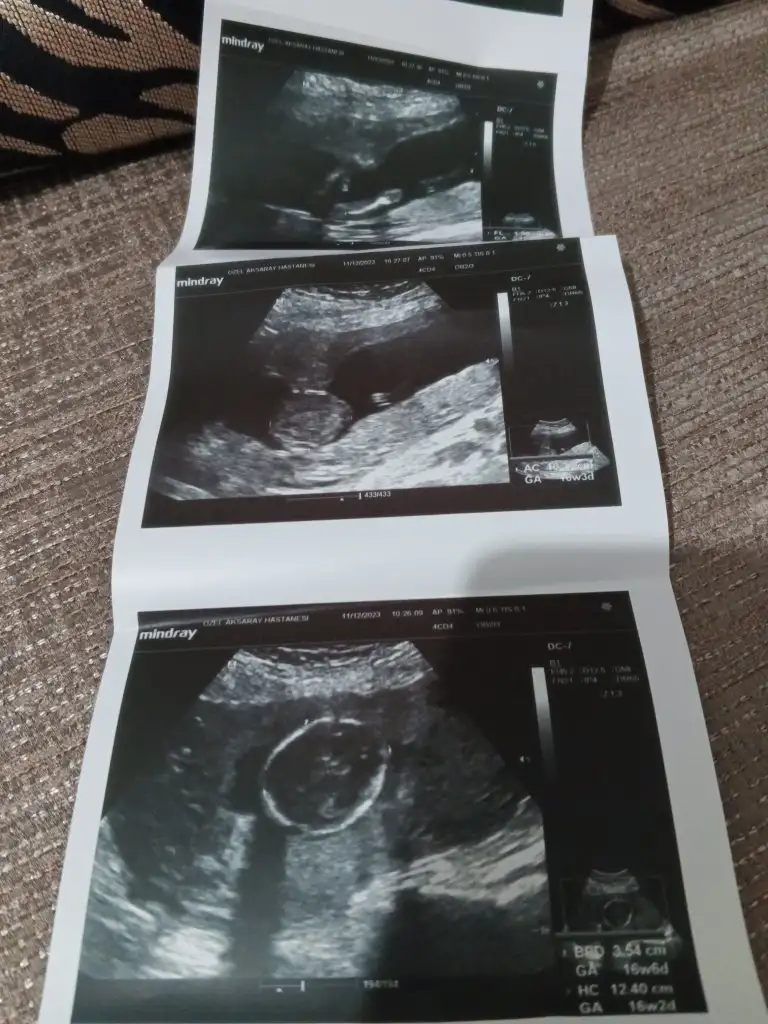

Sevde49 gönderdim bu resim geçen ayın... Dünkü doktor kontrolü ntrolunde çekilen resimleride attım bakarmisiniz sayfamda Allah rızası için

Eklentiler

• 17023915885283296783895134072047.webp

17023915885283296783895134072047.webp

39,9 KB · Görüntüleme: 152